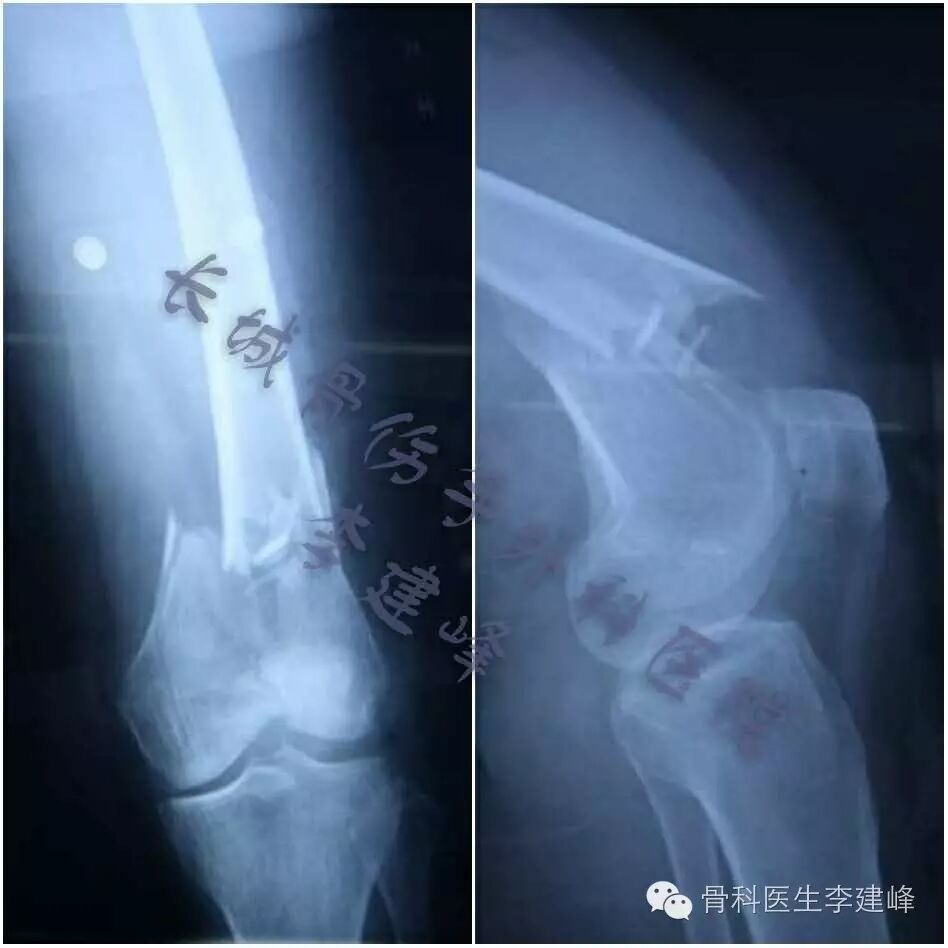

Four case:

术前

术后